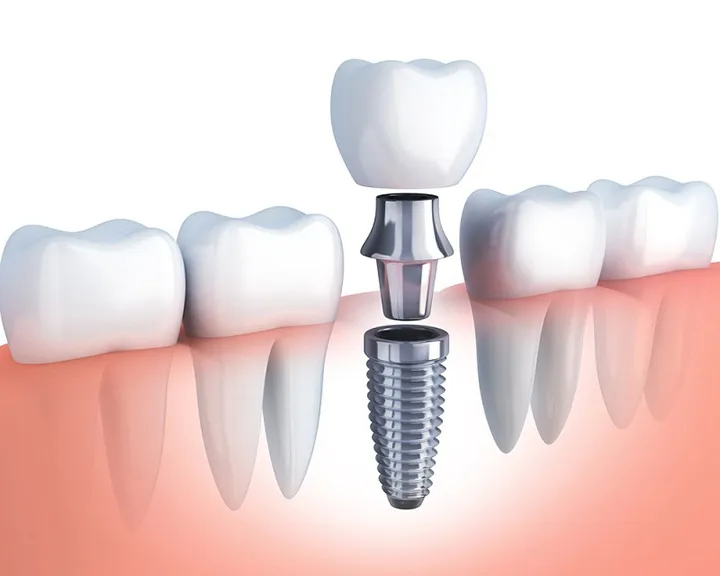

Chính vì vậy, việc phục hồi răng số 6 sớm là vô cùng cần thiết. Làm cầu răng số 6 là một giải pháp được nhiều người lựa chọn bởi tính hiệu quả và thẩm mỹ cao.

- Mong muốn phục hồi răng nhanh chóng và có chi phí hợp lý: So với cấy ghép implant, làm cầu răng thường có thời gian hoàn thiện ngắn hơn và chi phí thấp hơn.

- Chi phí hợp lý: So với các phương pháp phục hình khác như implant, cầu răng có chi phí thấp hơn.

- Thời gian điều trị ngắn: Quá trình làm cầu răng thường nhanh chóng hơn so với cấy ghép implant.

- Tuổi thọ không bằng implant: Cầu răng có tuổi thọ khoảng 5-15 năm, trong khi implant có thể tồn tại vĩnh viễn.

| Implant | Không mài răng, ngăn ngừa tiêu xương hàm, tuổi thọ cao, phục hồi chức năng nhai tối ưu | Thời gian điều trị lâu, chi phí cao, yêu cầu xương hàm đủ khỏe mạnh | 15.000.000 – 30.000.000 VNĐ/răng |